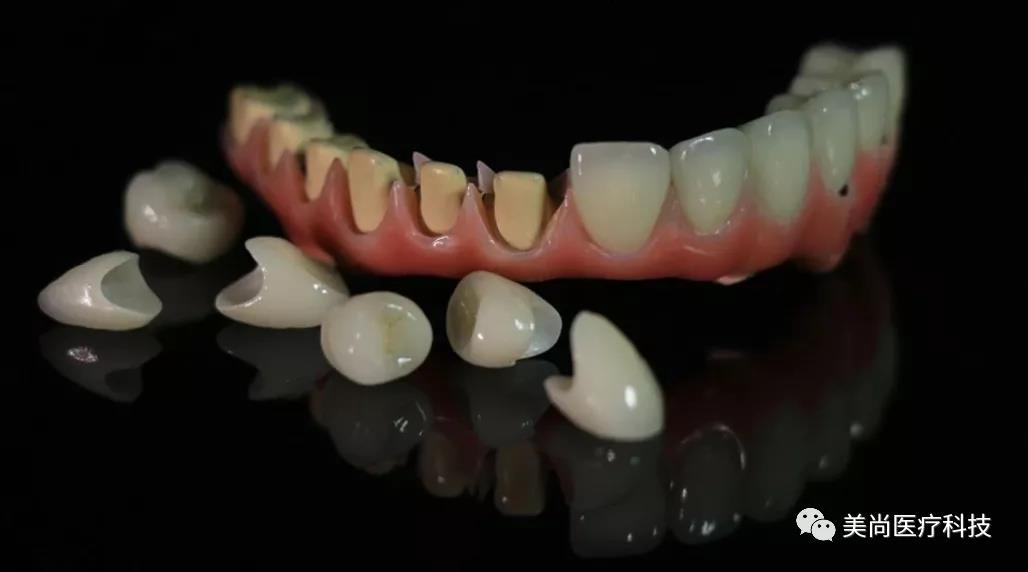

制作种植导板